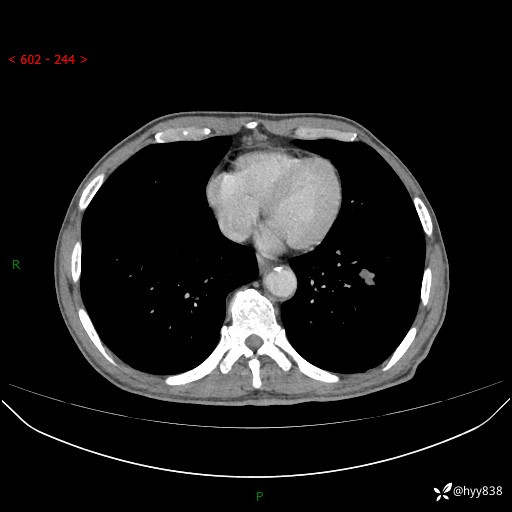

辅助检查:CT

胸部CT平扫

增强动脉期+静脉期

各期CT值:38Hu 52hu 55hu